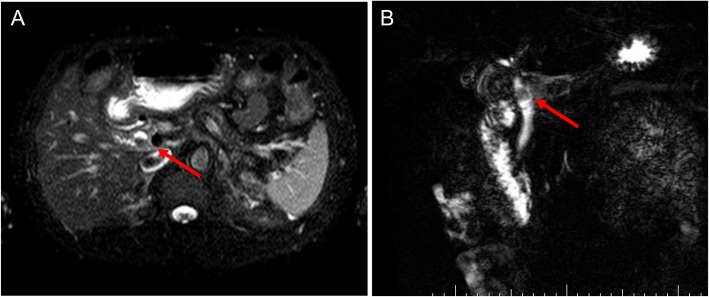

A 64-year-old man presented to our hospital with upper abdominal pain, jaundice, and anorexia. He had diabetes and was a social drinker but a lifetime non-smoker. Computed tomography (CT) scan revealed a dilated CBD, and acute cholangitis was suspected. The patient was referred to our hospital and admitted to the gastroenterology department for further investigation and treatment. Initial laboratory examinations revealed a white blood count (WBC) of 9770/μL, hemoglobin of 12.4 g/dl, increased C-reactive protein (CRP) of 5.47 mg/dl, total bilirubin of 7.75 mg/dl, AST/ALT of 176/281 IU/L, alkaline phosphatase of 815 IU/L, and ɤ-GTP of 132 IU/L. The serum tumor markers carcinoembryonic antigen (CEA) was within the normal range at 2.6 ng/ml and cancer antigen 19–9 (CA19–9) was elevated at 1162 U/ml. Both hepatitis B surface antigen (HBsAg) and antibodies to hepatitis C virus (anti-HCV) were negative. A plain CT scan on admission showed a high-density accumulation spreading throughout the CBD, and the entire CBD was dilated (Fig. 1). Gastroenterologists performed endoscopic retrograde cholangiopancreatography (ERCP) and endoscopic sphincterotomy (EST), during which a hematoma in the CBD was discovered. This revealed the reason for obstructive jaundice was not choledocholithiasis but the hematoma, which was subsequently drained through the incised Vater’s papilla (Fig. 2). A few days later, enhanced CT scan and magnetic resonance cholangiopancreatography (MRCP) were performed, and they showed improved dilation of the CBD and enhanced wall thickness of the bile duct measuring 25 × 10 mm at the union of the cystic and common hepatic ducts (Figs. 3 and 4). A cholangioscope detected an elevated tumor covered by sludge in the CBD (Fig. 5). The mucous membrane around the tumor showed redness and a malignant tumor was suspected. The result of the tumor biopsy revealed no malignant features in the histology, but the possibility of CC could not be denied from the macroscopic findings. We were consulted for surgical resection and performed an extrahepatic bile duct resection and cholecystectomy. Intraoperative rapid pathological diagnosis was performed, and we confirmed that the surgical margins in both the pancreatic and hepatic sides were cancer-free. The postoperative course was uneventful. The resected tumor had irregular elevated mucosa with an ulcerated lesion (Fig. 6a). The pathological examination of the resected tumor revealed that the ulcerated lesion had inflammatory granulation tissue; however, it did not contain the components of invasive carcinoma (Fig. 6b). Many consecutive intraepithelial micropapillary lesions spread around the ulcerated lesion, and the epithelial cells showed increased nucleus-to-cytoplasm ratio, nuclear hyperchromasia, and architectural atypia (Fig. 6c). The pathological diagnosis was BilIN-1 to -2. It also revealed that the BilIN-1 lesion spread through both the pancreatic and hepatic margins. Immunohistochemical staining showed that S100P was slightly expressed in the cytoplasm and MUC5AC was positive, while MUC1 was negative and p53 was not overexpressed (Fig. 6d–g).